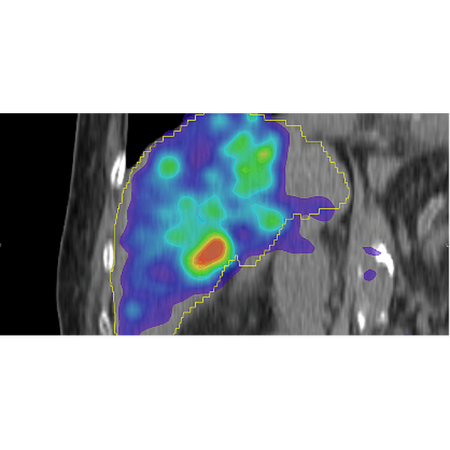

Post-Therapy Dosimetry

MIM SurePlan LiverY90 provides tools for dose calculation using Y90-PET and Bremsstrahlung SPECT. This allows you to calculate isodose curves/DVH on PET/SPECT using Local Deposition Method or the Voxel S Value approach based on the schema in MIRD Pamphlet No. 17. Therapy response evaluation is possible with automated tools for serial exam comparison.